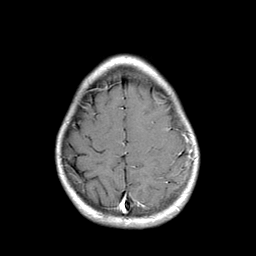

Metastatic bronchogenic carcinoma: T1-weighted MR -- Slice #19

[Home][Help][Clinical] Slice 19